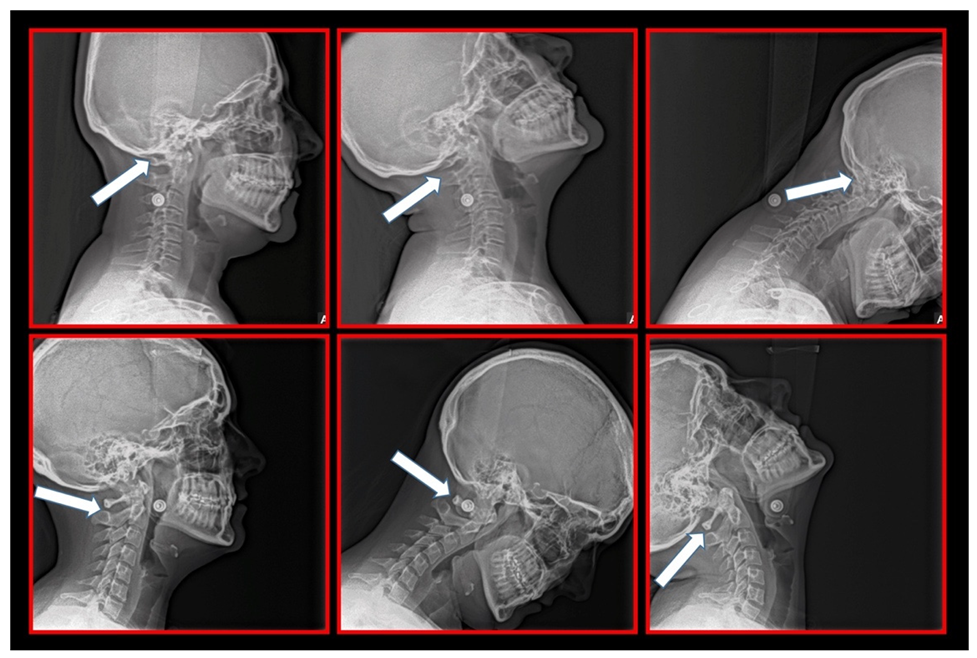

11.5. Axis and Atlas Derotation